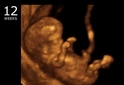

Gebelik, birçok fizyolojik değişikliklerin yanı sıra bazı komplikasyonları da beraberinde getiren bir süreçtir. Bu süreçte, kanama, hem anne hem de fetüs için önemli bir risk faktörü oluşturabilir. Gebelikte kanamanın nedenleri, erken dönem ve geç dönem şeklinde iki ana gruba ayrılabilir. Bu makalede, gebelikte kanamanın olası nedenleri üzerinde durulacak ve her bir nedenin klinik önemi ele alınacaktır. Erken Dönem Kanama NedenleriErken dönemde meydana gelen kanama, genellikle 20. gebelik haftasından önce gerçekleşir ve aşağıdaki nedenlere bağlı olarak gelişebilir: